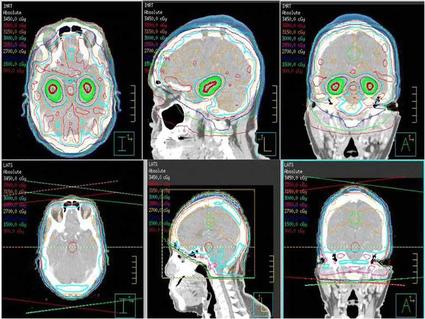

It may even make sense to combine radiopharmaceuticals with external radiation, as long as careful treatment planning can ensure a safe overall radiation dose, added Dr. Capala. “External radiation therapy is very good at targeting large tumors, and then you could combine it with radiopharmaceutical therapy to target metastases,” he said.